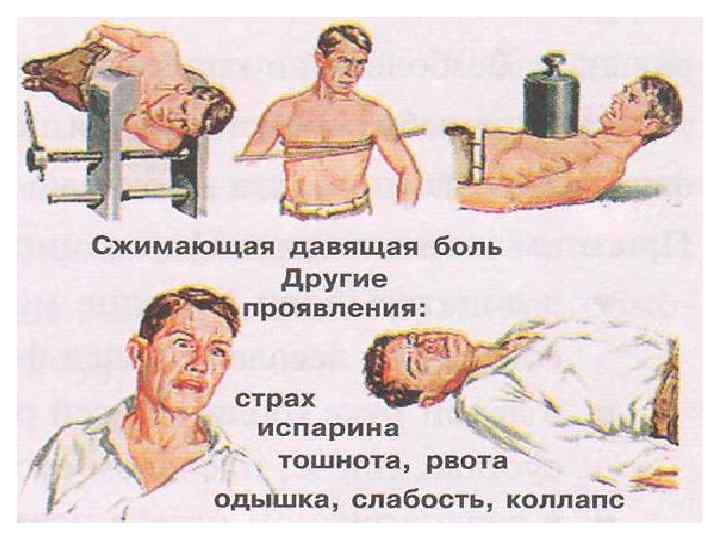

КЛИНИЧЕСКИЕ ПРОЯВЛЕНИЯ И ДИАГНОСТИКА. • Приступы стенокардии провоцируются незначительными (малыми) физическими и/или эмоциональными нагрузками, метеофакторами, колебаниями АД, приемом алкоголя, приемом пищи, ПТА. • Характерна меньшая интенсивности и большая продолжительность ангинозных приступов. • Характерны клинические эквиваленты ангинозных приступов: астматический, аритмический, гастралгический, цереброваскулярный, коллаптоидный. Чаще наблюдается безболевая ишемия миокарда. Высокая частота «атипичных» клинических проявления стенокардии в пожилом возрасте объясняется атеросклеротическим поражением различных сосудистых бассейнов.

КЛИНИЧЕСКИЕ ПРОЯВЛЕНИЯ И ДИАГНОСТИКА (2). • Аритмический вариант стенокардии нередко проявляется синдромом МАС. Резкое снижение сердечного выброса при этом приводит к расстройствам гемодинамики (аритмогенный шок) и церебральным расстройствам вплоть до развития ОНМК и комы. При этом риск внезапной смерти резко возрастает и составляет 20 -25% в год. • Часто наблюдается дизадаптационная (холодовая) стенокардия и стенокардия de cubitas. • На клинические проявления стенокардии в пожилом возрасте существенное влияние оказывают хронические заболевания: СД, анемия, ГБ, ХНЗЛ, язвенная болезнь желудка, хронический панкреатит, хронический холецистит, ДЭ, абдоминальный ишемический синдром и др.

КЛИНИЧЕСКИЕ ПРОЯВЛЕНИЯ И ДИАГНОСТИКА (3). • Прогностически неблагоприятны следующие клинические формы стенокардии: - Стенокардия напряжения III – IV ФК. - Стенокардия de cubitas. - Вариантная (вазоспастическая) стенокардия. - Стенокардия покоя, сопровождающаяся одышкой, ЖНРС, потерей сознания.